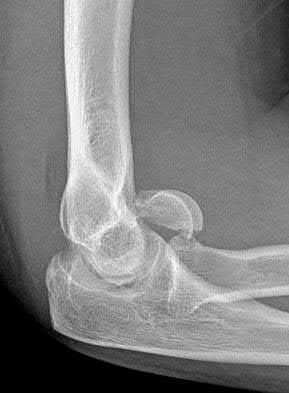

1020) Figures 108a through 108c are the radiographs of a 38-year-old man who fell on an outstretched hand 1 week ago and now reports severe left elbow pain. Examination of the wrist reveals normal range of motion with no tenderness or swelling. Pain limits examination of his elbow. What is the most appropriate management to determine if surgery is indicated?

5. Intra-articular lidocaine injection followed by repeat examination Corrent answer: 5

Whereas there is controversy regarding the best treatment for comminuted radial head fractures, nondisplaced and minimally displaced fractures in which there is no block to motion can be treated nonsurgically. At the time of initial examination, it is important to determine that there is no block to range of motion. If pain limits the ability to examine the patient's range of motion, local analgesia with intra-articular lidocaine is most appropriate. Whereas general anesthesia would be useful for open reduction and internal fixation, the necessity for open reduction and internal fixation is best determined first before scheduling surgery. Neither a CT or MRI scan is necessary if the patient has no block to range of motion. Early range of motion is the best treatment for radial head fractures treated nonsurgically. After immobilization for 2 weeks, it may be difficult to determine whether there is a block to motion because the patient will likely have decreased elbow pronation and supination.